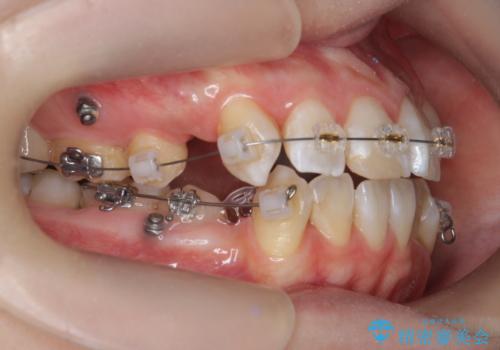

- 矯正装置

- ワイヤー矯正

- 2年8ヶ月

前歯の角度を改善するために小臼歯4本の抜歯を行いワイヤー マルチブラケットを用いて、しっかりと前歯の角度を改善する治療計画としました。

綺麗な歯並びを手に入れられたと同時に、口元もスッキリし、仕上がりに満足いただくことができました。